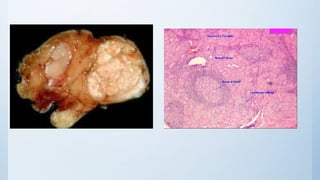

MP : dormant nodule (fibrous tissue capsule with

necrotic tissue, area of Haemorrhage & destroyed thyroid follicles)

1.clinically apparent solitarynodule on top of MNG: Clinically: STN US: MNG pathology :NE :STN MP : dormant nodule (fibrous tissue capsule with necrotic tissue, area of Haemorrhage & destroyed thyroid follicles) complications & ttt :as MNG